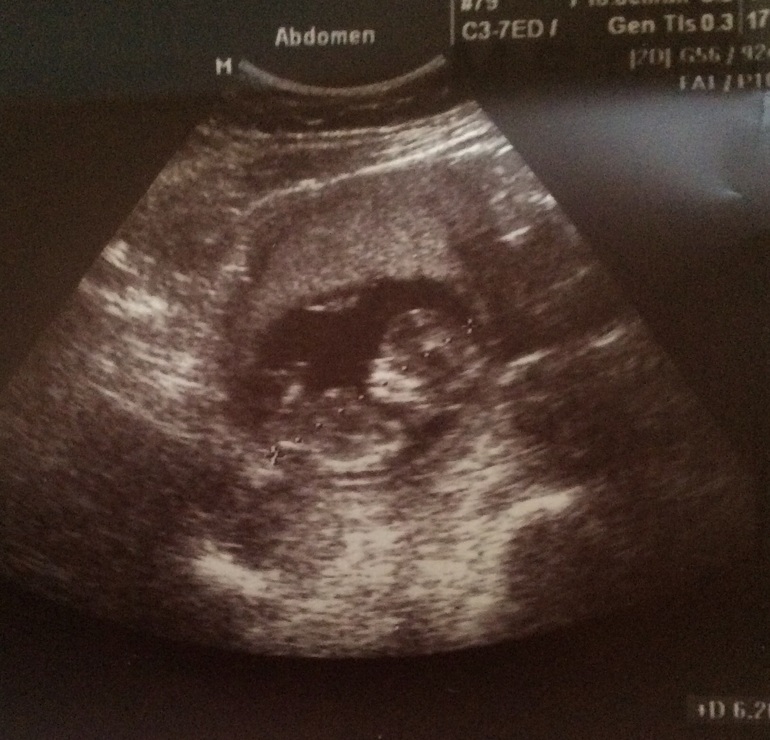

13 недель

Померили нам все) не слишком ли мы бошковитые и носатые?)) и случайно ли не девочка мы судя по торчку?)

А носик где? Не вижу данных) про остальное все хорошо) пол определять не умею, так что тут я не советчик)))